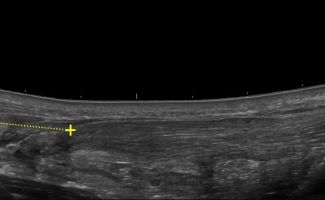

- Plantar Fasciitis

- Plantar Fibromatosis